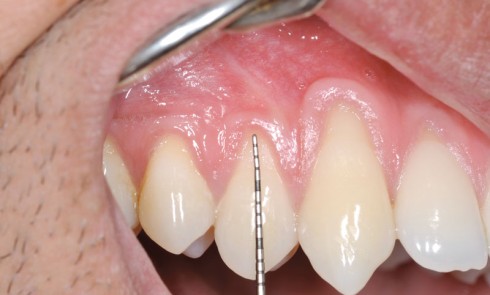

Article réservé à nos abonnés Greffe épithélio-conjonctive ou greffe conjonctive enfouie ?

Un complexe muco-gingival pathologique est celui où les tissus gingivaux ne maintiennent plus une attache durable à la dent et...